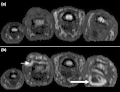

Magnetic resonance images of the fingers in psoriatic arthritis. Shown are T1 weighted axial (a) pre-contrast and (b) post-contrast images exhibiting dactylitis due to flexor tenosynovitis at the second finger with enhancement and thickening of the tendon sheath (large arrow). Synovitis is seen in the fourth proximal interphalangeal joint (small arrow).